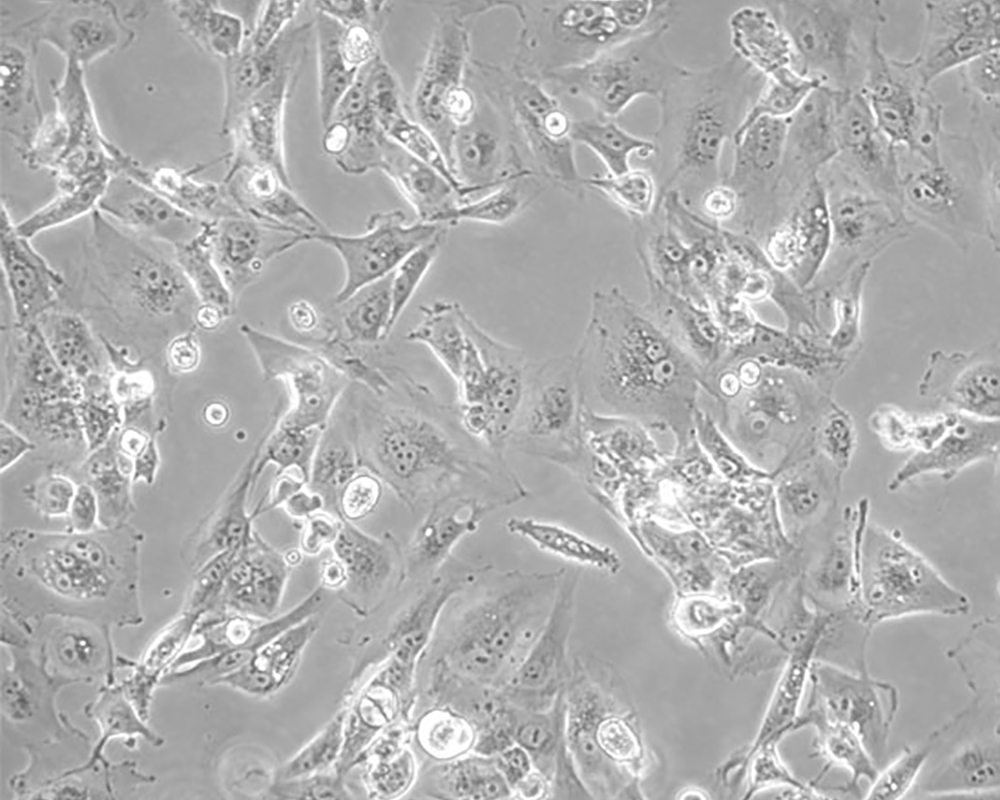

Caki-1

中文名稱 人腎透明細胞癌皮膚轉(zhuǎn)移細胞

組織來源 腎透明細胞癌;皮膚轉(zhuǎn)移;男性

形態(tài)特征 epithelial

細胞描述 該細胞超微結(jié)構(gòu)中包含許多微絨毛、少許微絲、許多小線粒體、發(fā)達的高爾基休和內(nèi)質(zhì)網(wǎng)、許多脂滴和多層體、次級溶酶體,沒有發(fā)現(xiàn)病毒顆粒。